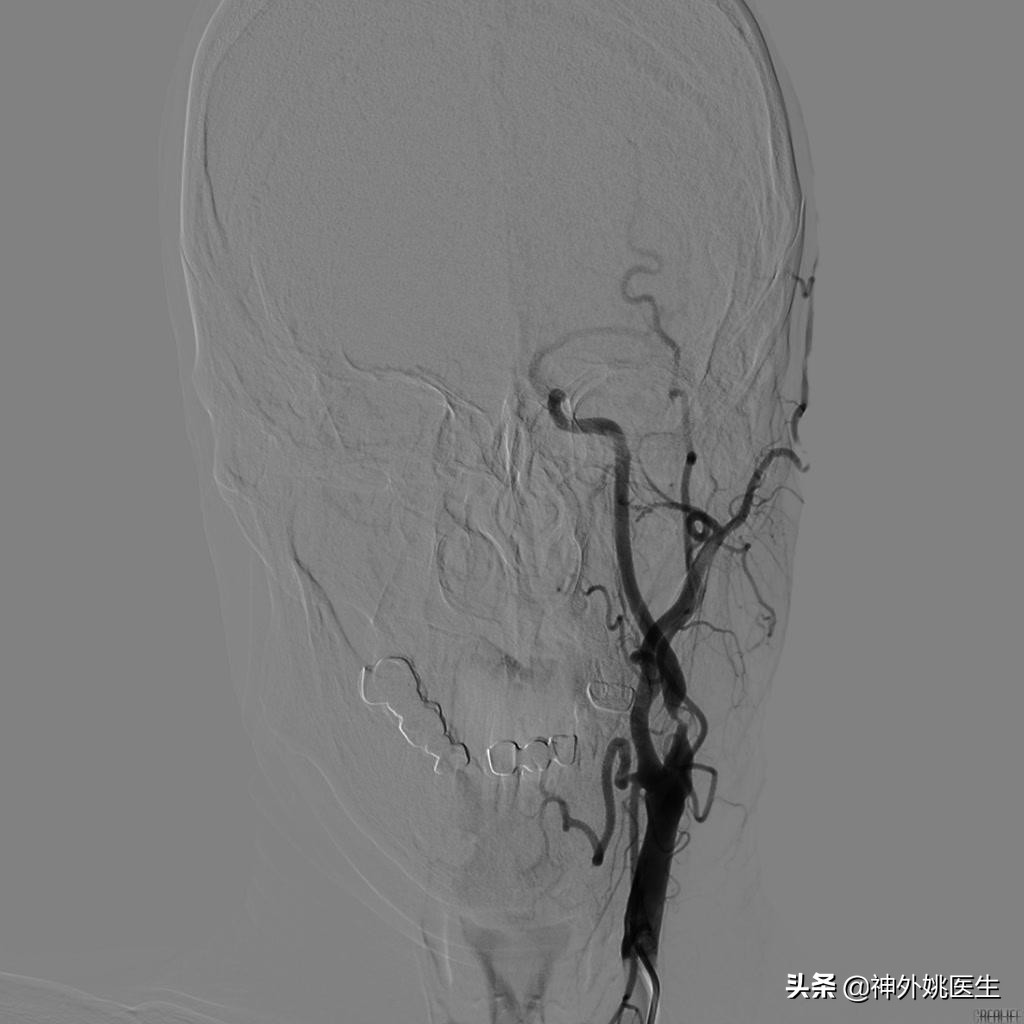

术前DSA检查:(图3-6)

图3 左颈内动脉起始段重度狭窄。